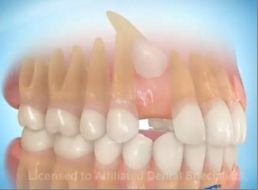

Carga Imediata

Para muitos pacientes, a necessidade de estar sem a prótese durante um período de tempo, após a instalação dos implantes, pode ser considerada inconveniência em função do convívio social e atividades profissionais. O termo carga imediata pode ser definido como instalação de implantes osseointegrados em condições ideais à estabilidade primária, seguida de ativação protética ( colocação dos dentes ) 48 horas após a cirurgia. Esta definição era aplicada à instalação de múltiplos implantes dentários e a contenção entre os mesmos promovendo um efeito de estabilidade. Com estudos recentes podemos colocar o implante unitário e colocar o dente no mesmo instante, sendo observado somente uma boa estrutura óssea.

Quanto tempo leva para ser feito ?

O processo leva cerca de 2 ou 3 dias variando de acordo com o número de dentes a serem implantados no paciente. Em reabilitações totais, na média, são realizados 6 a 8 implantes para cada arcada ( superior ou inferior ) em uma única sessão cirúrgica. Com o modelo em mãos é confeccionada a infra-estrutura que é provada em uma sessão, normalmente no dia seguinte a cirurgia. A infra-estrutura volta ao laboratório onde recebe os dentes. Depois a peça pronta é colocada.

Podemos prever o resultado ?

Observando o estudo comparativo entre a técnica convencional estabelecida por BRANEMARK e o protocolo de carga imediata temos como grandes vantagens a diminuição do tempo das consultas e a rapidez dos resultados oferecidos ao paciente, com efeito psicológico e social melhorados, já que os resultados geram bem estar funcional e estético. Os pacientes devem ser selecionados e a indicação estabelecida após controle sistêmico da saúde e das condições locais favorecidas para essa técnica. Comparada com a técnica convencional onde o paciente esperaria normalmente de 3 a 6 meses para a colocação dos dentes, a técnica da carga imediata pode ser uma ótima opção.